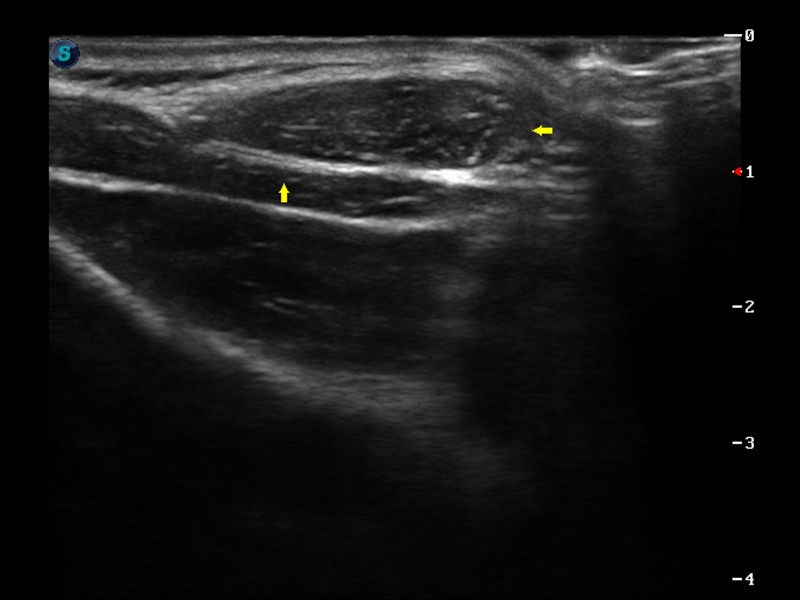

S9便携式彩色多普勒超声诊断仪是球速体育入口研发的高端便携彩超设备,外观设计新颖、产品性能卓越。S9在便携超声领域采用了突破传统的触摸屏交互设计,并以先进的软件硬件技术和设计理念,为您带来清晰的图像质量、稳定的工作性能和便捷的操作体验。

μ-Scan微米成像